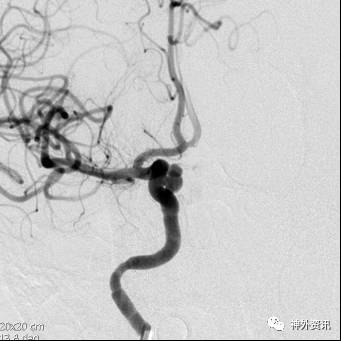

病例一

病例二

病例三

病例四